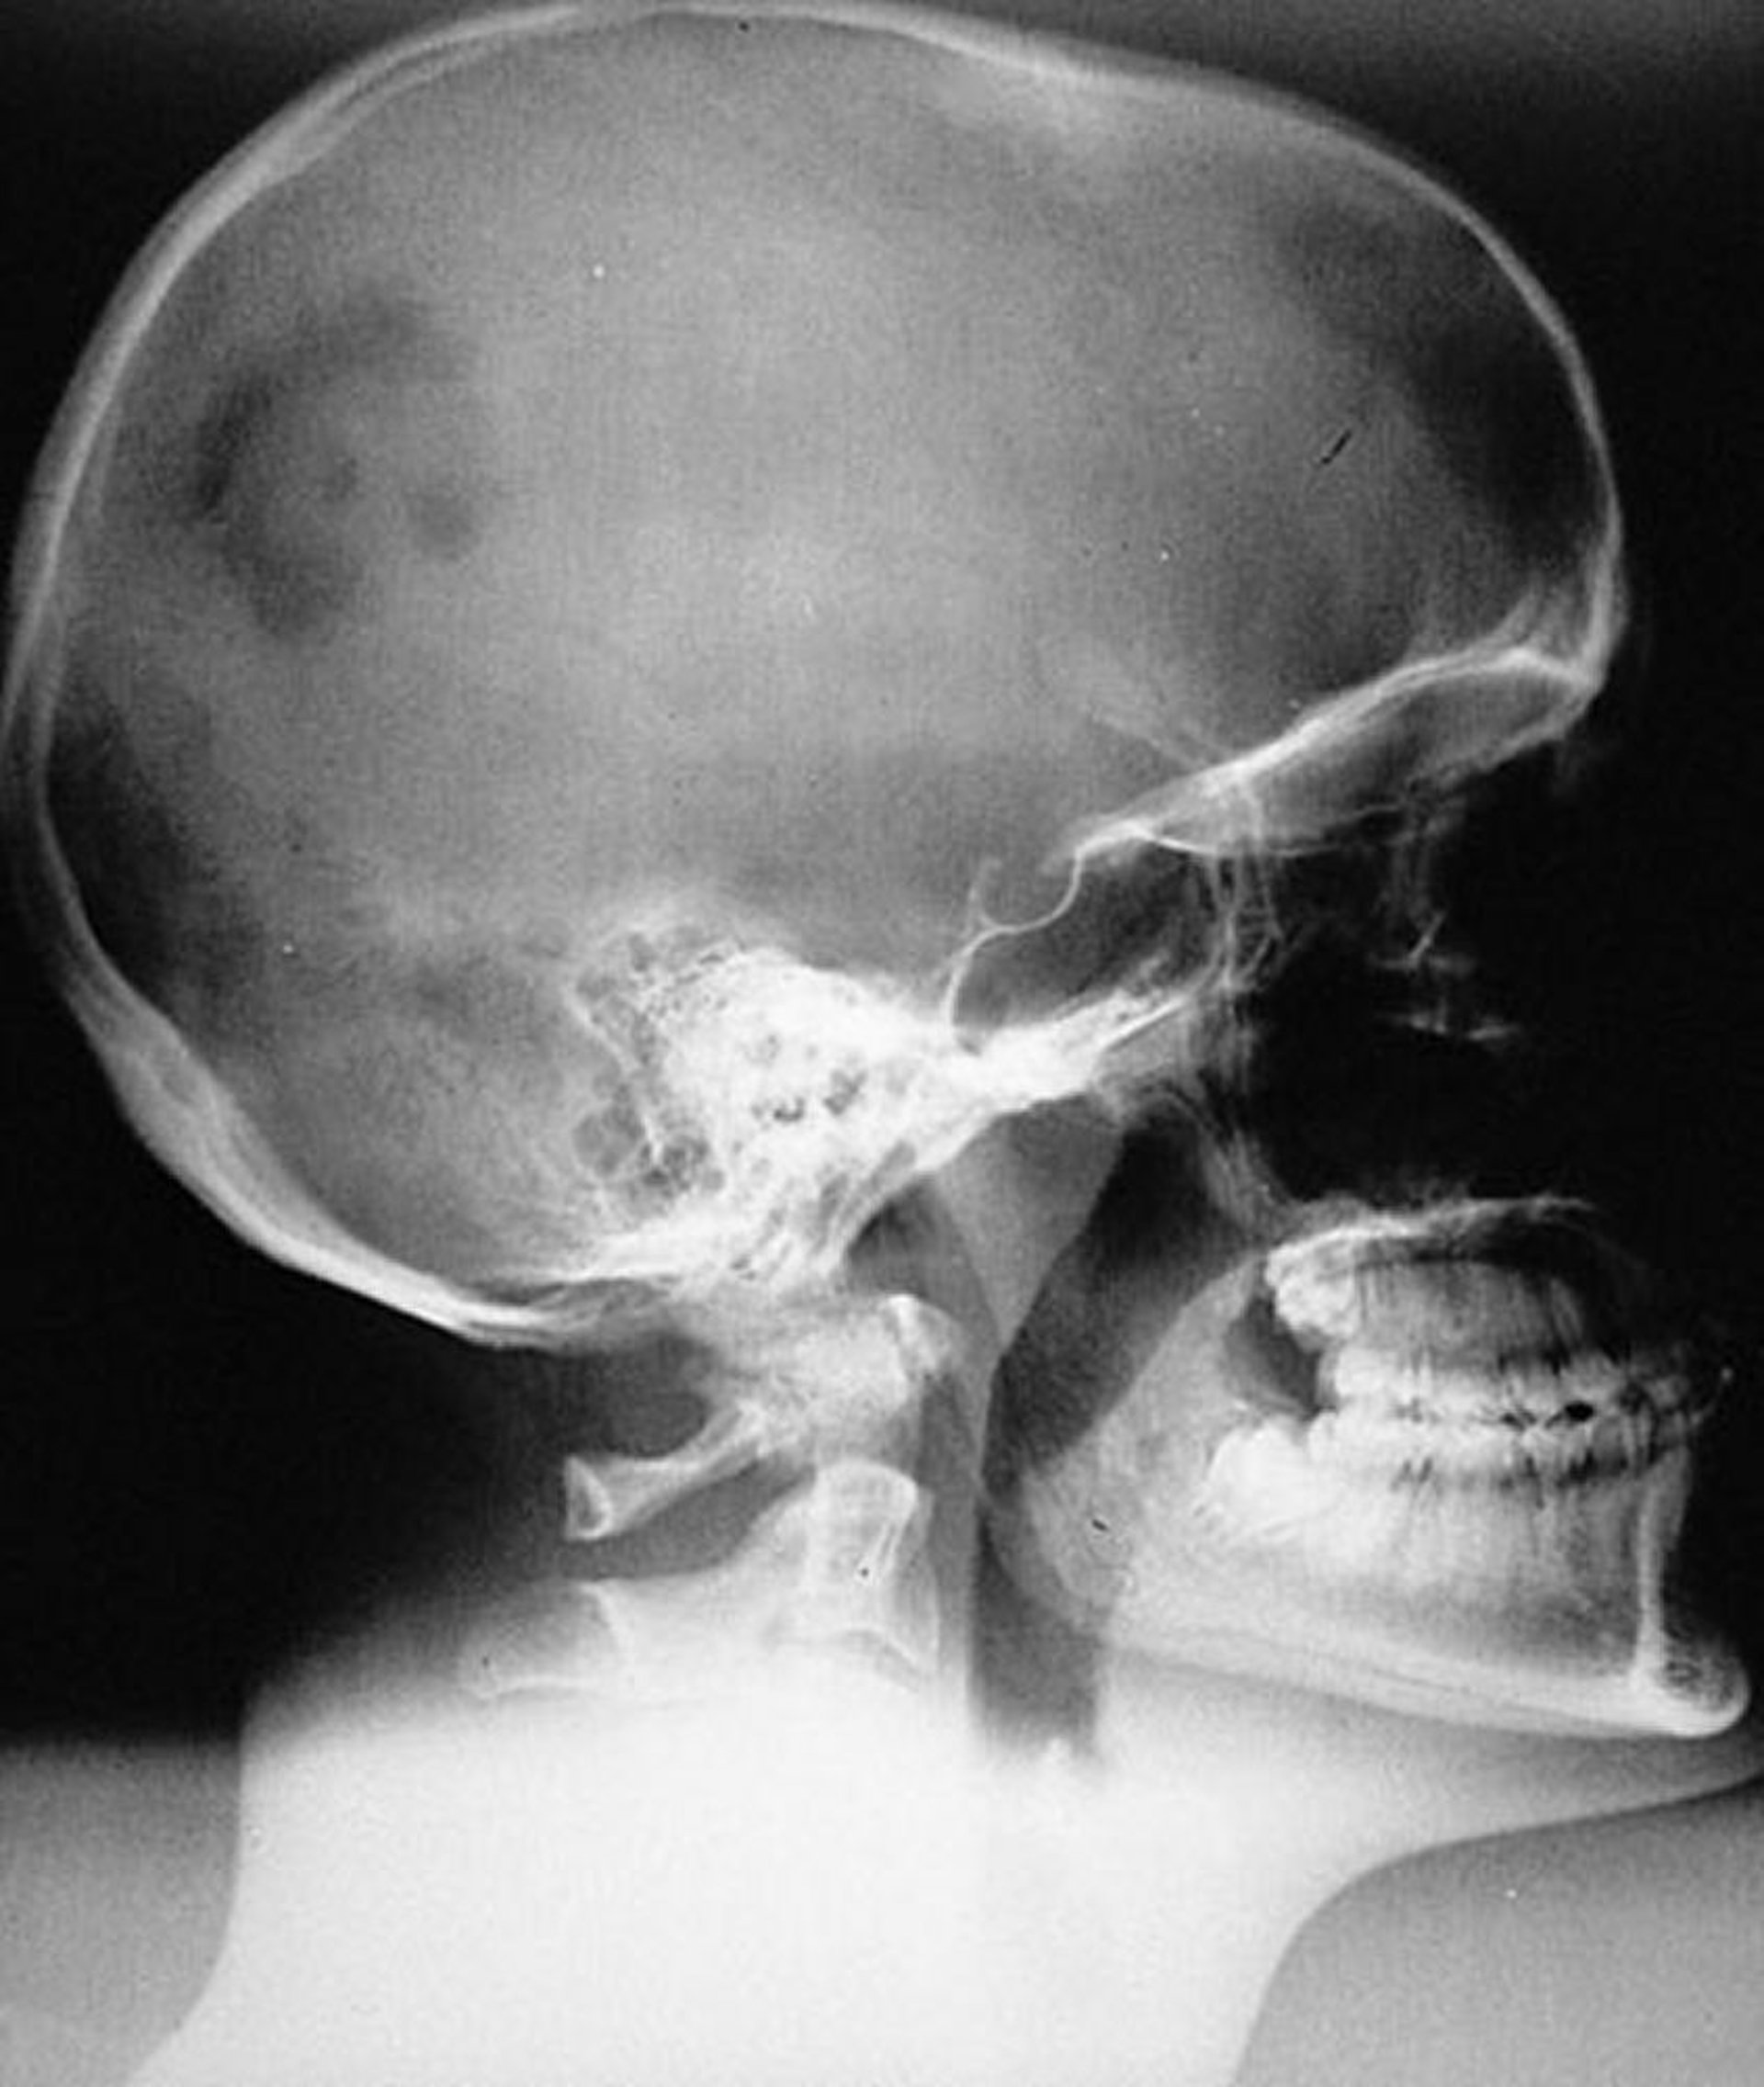

Istiocitosi a cellule di Langerhans (granuloma eosinofilo) del cranio

Aspetto radiografico della tipica lesione monostotica unifocale dell'istiocitosi a cellule di Langerhans (granuloma eosinofilo) del cranio. La lesione è nettamente marginata ma non smussata.

By permission of the publisher. From Swearingen B, Schaefer P, Primavera J, Klibanski A. In Atlas of Clinical Endocrinology: Neuroendocrinology and Pituitary Disease. Edited by S Korenman (series editor) and ME Molitch. Philadelphia, Current Medicine, 2000.